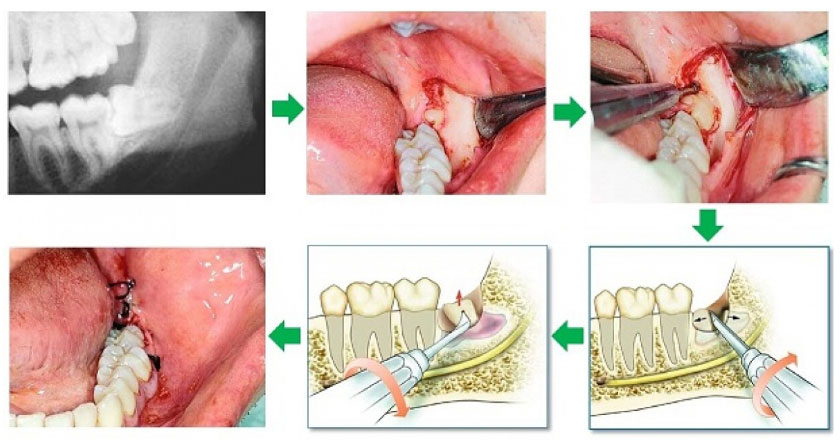

Nha khoa Nhân Tâm là phòng khám nha khoa chất lượng tại quận 10, ứng dụng công nghệ nhổ răng siêu âm Piezotome hiện đại, đảm bảo nhổ răng an toàn, không đau và tạo cảm giác thoải mái cho bệnh nhân trong quá trình nhổ răng.

Công nghệ siêu âm Piezotome sử dụng linh hoạt bước sóng siêu âm từ 28 – 36 Khz, chỉ tác động lên các mô cứng để nhổ bỏ răng, bảo vệ mô mềm trong khoang miệng.

Đặc biệt, công nghệ siêu âm sẽ không tác động lên dây thần kinh và mạch máu quanh chân răng, không làm tổn thương đến xương hàm hoặc nướu răng. Quá trình nhổ răng nhẹ nhàng, không đau, không sưng, không biến chứng và bệnh nhân vẫn có thể nói chuyện và ăn uống bình thường sau khi nhổ răng.

Đối với răng mọc ngầm, mọc ngang hoặc có kích thước lớn, công nghệ siêu âm sẽ hỗ trợ Bác sĩ phân nhỏ răng để dễ lấy ra khỏi nướu. Nhờ hạn chế chảy máu, tốc độ lành vết thương của bệnh nhân cũng nhanh hơn so với kỹ thuật nhổ răng khôn truyền thống.